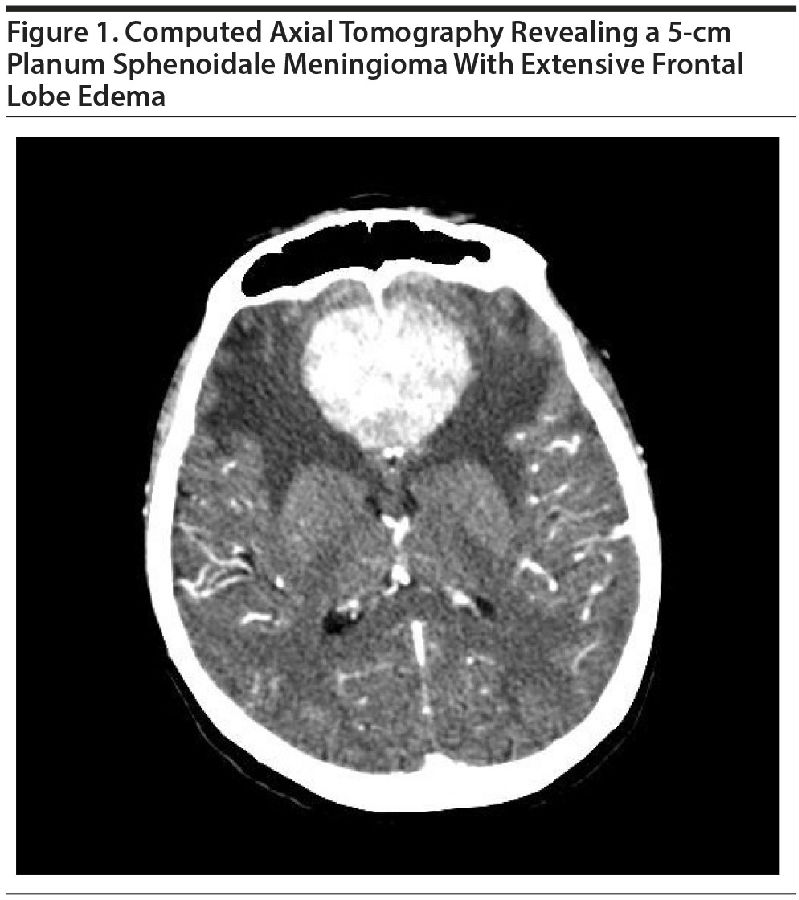

蝶骨平台处可见一5cm肿瘤,伴广泛的额叶水肿(LeoRJ,2016)

实验室检查未能发现足以解释患者上述异常的结果。头颅CT提示,蝶鞍前部的蝶骨平台存在一5cm大小的肿块,额叶存在广泛水肿(如上图)。磁共振成像进一步确认了肿块的存在,其体积较大,高度血管化,考虑为嗅沟脑膜瘤。遂请神经外科会诊,行双额开颅手术以切除肿块。患者谵妄消失,先前“精神分裂症”所导致的症状在为期1年的随访内未再出现;抗精神病药也已停用。